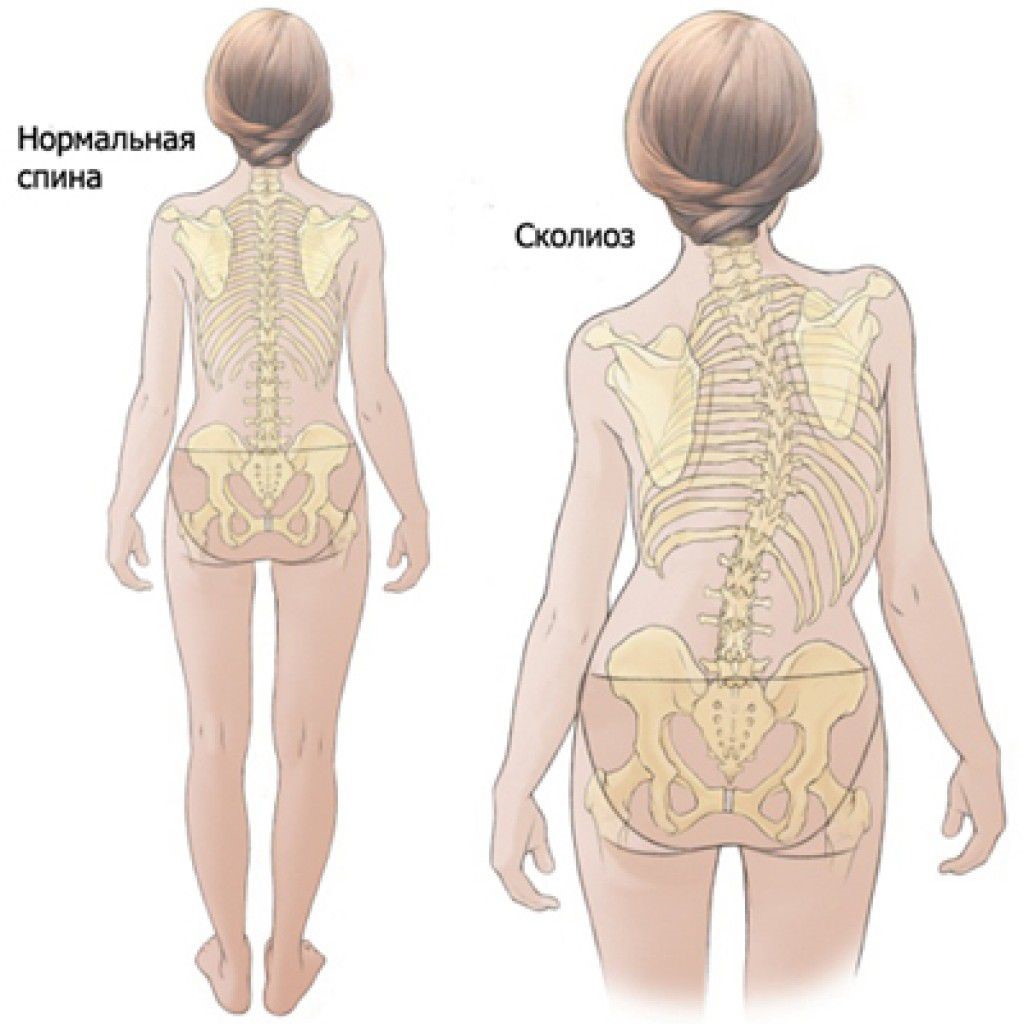

Искривление позвоночника: причины и последствия на снимках

Раздел: Визуальный дайджест